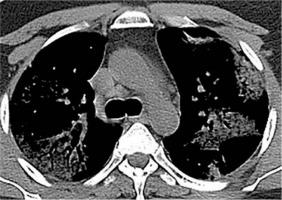

Ground glass opacity (GGO) is described as hazy areas with slightly increased density in the lungs, but with unobscured bronchial and vascular margins. This is attributed to the partial filling of alveoli by exudate and alveolar septal inflammation. GGO is the most widely reported radiological sign linked to COVID-19. It is considered one of the earliest signs to appear in CT in the pre-clinical group (asymptomatic) and extends to predominate in the second and third weeks as well. GGO in COVID-19 has a characteristic distribution being peripheral (subpleural), often bilateral, multifocal, possibly nodular or mass-like, and predominantly affecting lower lung lobes. The last feature could be explained by the fact that diseased patients are likely to move less and prefer to lie down, so they develop radiological changes in the most dependent areas of the lungs. Extensive bilateral diffuse GGO (also named bilateral white lungs) is noted in severe cases that may require admission to the intensive care unit (ICU) and intubation [11-16] (Figure 1).

Figure 1

Ground glass opacity (GGO). A) High-resolution computer tomography (HRCT) shows GGO with air bronchogram at the posterior segment of the right upper lung lobe with thickening of the oblique fissure. There is inter- and intralobular septal thickening overlying the GGO at the anterior segment of the left upper lung lobe crazy paving (black arrow). B) HRCT shows bilateral diffuse extensive GGO (white lung sign) with air bronchogram and small consolidation at the posterior basal segment of the left lower lung lobe